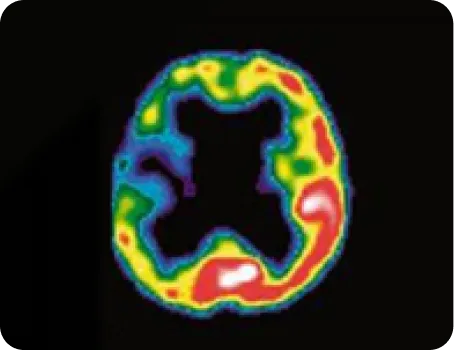

우측 중대뇌동맥 폐색 환자의 3주 후

SPECT(뇌 혈류 역학 검사) 사진

침 치료 8일 후 증가된 혈류

침 치료 후 증가된 뇌경색 주변부 혈류량